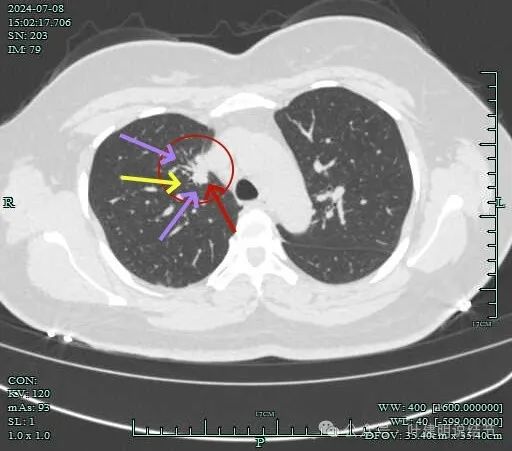

再看2024年7月份的影像:

病灶纵隔窗上是软组织影,表面不平,形态不规则。上腔静脉旁有肿大淋巴结。

病灶膨胀性不明显。

邻近支气管有扩张,表面不平,分叶明显。

灶边部分细支气管扩张,腔静脉旁淋巴结较大

病灶有血管与之相连,淋巴结更显得明显了。

肺窗上见与上腔静脉紧贴着,病灶边缘稍显模糊。

病灶边上不清爽。

病灶有毛刺与小棘突征,有邻近细支气管扩张,表面不平,膨胀性不明显。

毛刺征明显,灶边细支气管扩张。

病灶整体轮廓还是较为清楚的。